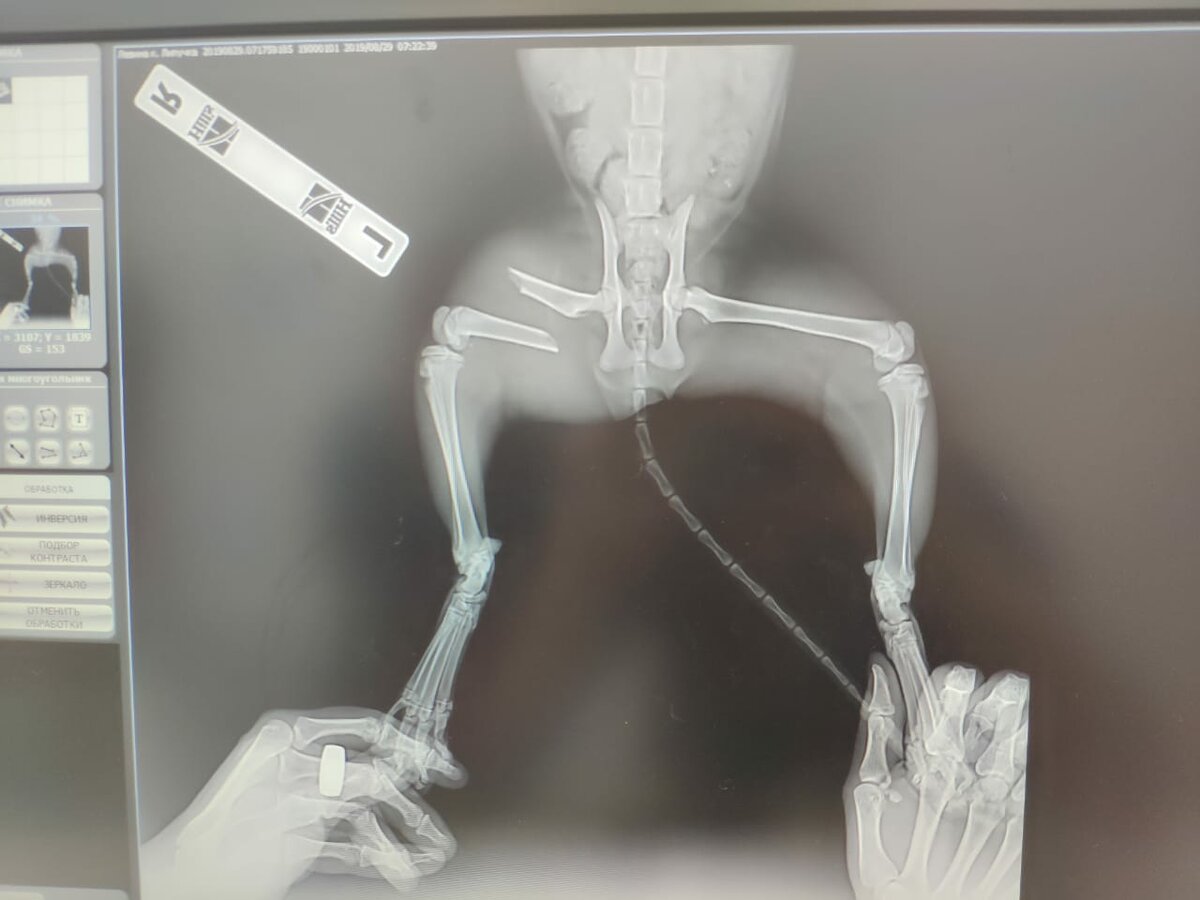

Однажды мы заметили что она ползёт, а не идет и задняя правая лапа завёрнута под себя. Мы поехали в вет.клинику где на рентгене показало что у нее сломано бедро и ей нужна срочная операция.

В ходе операции ей установили штырь который помогал кости срастись правильно. Общая цена за рентген, операцию и лекарства составила около 15 тыс. рублей